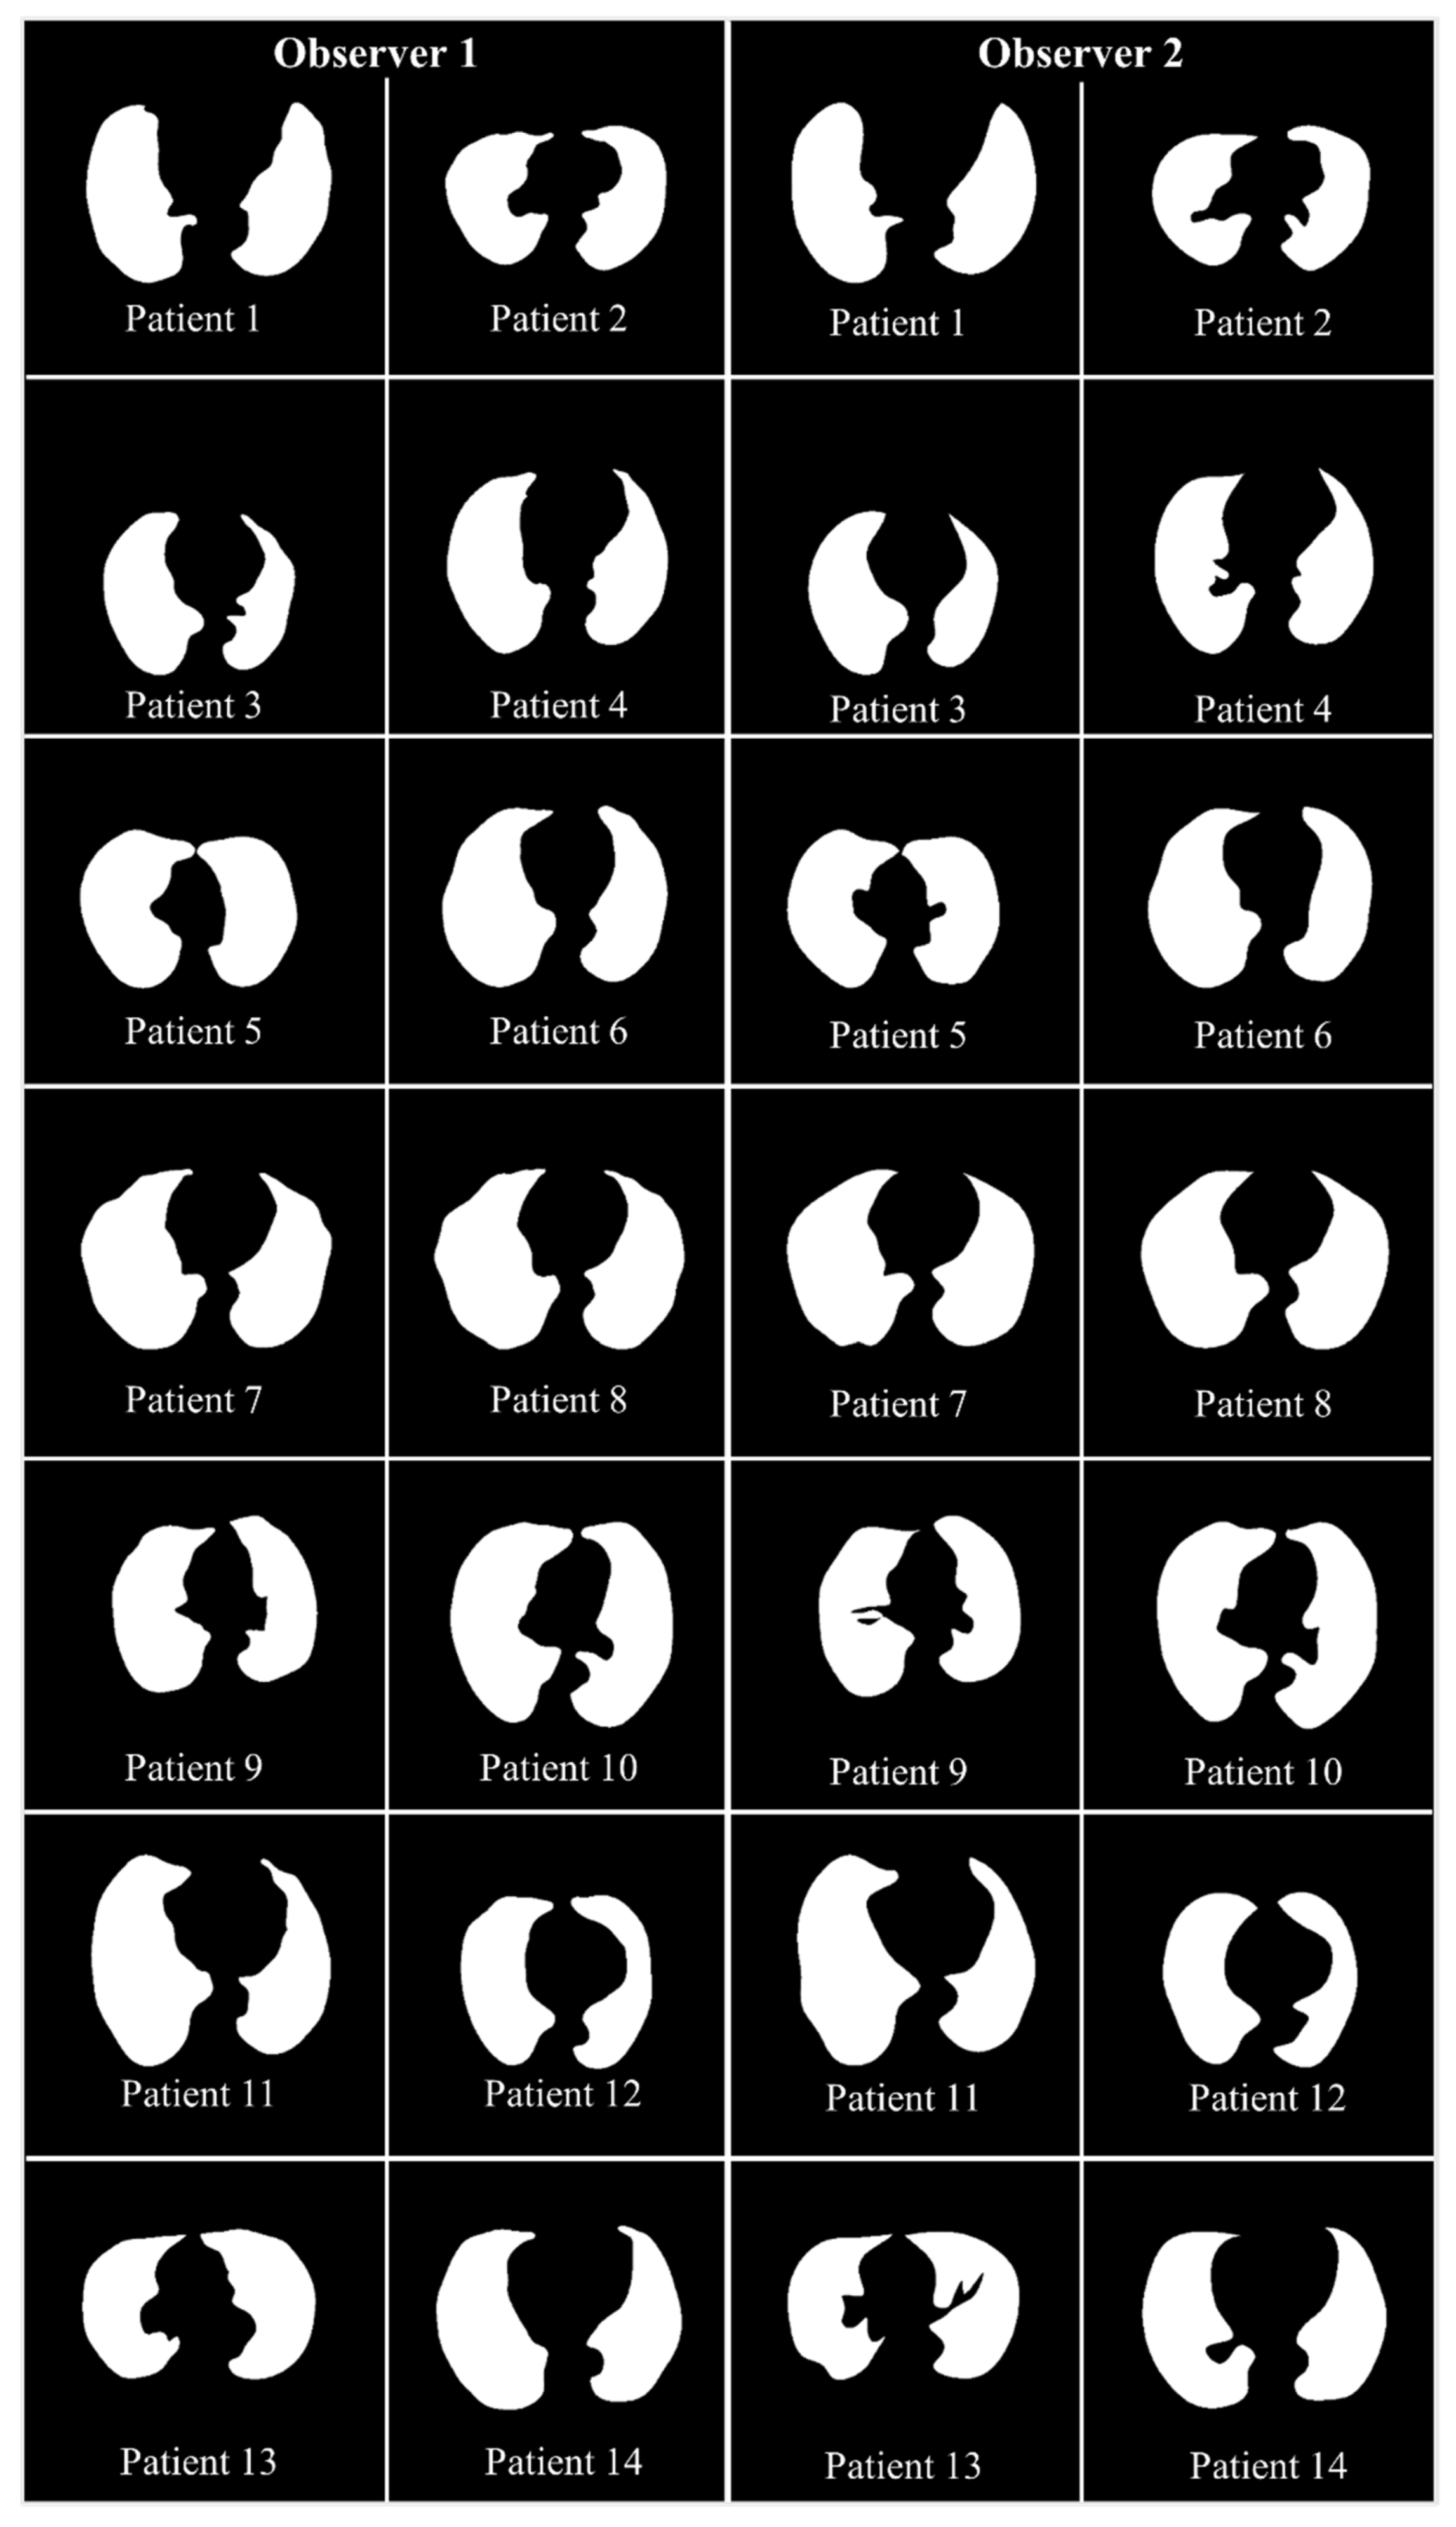

2.1. Patient Demographics, Image Acquisition, and Data Preparation

2.1.1. Demographics

2.1.2. Image Acquisition

2.1.3. Data Preparation

4.1. Results

4.2. Performance Evaluation

4.2.1. Lung Boundary and Long Axis Visualization